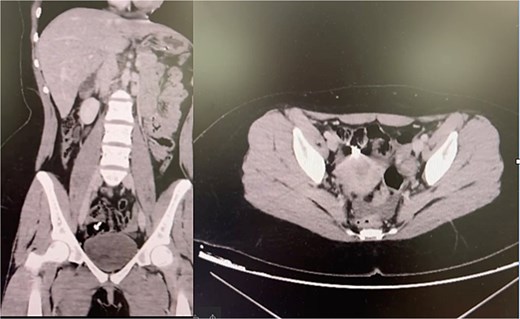

A 14-year-old boy with mild ID ingested a detachable plastic doll arm during repetitive self-stimulatory play. Initially asymptomatic, he developed bilious vomiting, abdominal distension, and constipation 3 days later. Examination revealed dehydration, periumbilical tenderness, and distension. Abdominal radiographs showed multiple air–fluid levels suggestive of small bowel obstruction, but no foreign body was visualized. Computed tomography (CT) confirmed a radiolucent intraluminal mass in the distal jejunum (Fig. 1).

Teaching point: Radiolucent plastics are often invisible on plain films; CT should be performed early in adolescents with unexplained small bowel obstruction [6].